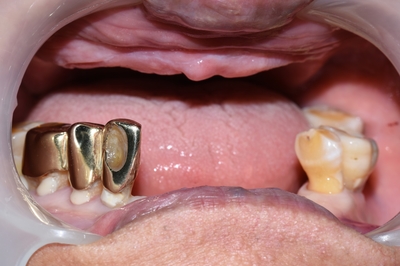

하기 전과 비교해볼까요?

저희 치과에서 시술하시기 전 모습입니다.

![[종로/시청역]실제 환자의 보험 임플란트, 보험 틀니 사례 소개합니다. 젊어지는틀니,임플란트 치료 관련 이미지 10](https://pub-9f2bb3498faf4d1d8714b41df24753e3.r2.dev/content/clinics/archive/rseeanjxfu/naver_blog/yonseiyegam/assets/by_hash/3d8b9018a1ff8a8b91568f131d8f468ded2ac07a2be2fa7adcd249dcfaf51d1e.png)

야매 틀니를 다 뺀 사진과 야매 틀니를 하고 입을 다문 옆모습입니다. 틀니를 끼고 있어도 윗 입술 부분이 꺼져보여 좋지 않습니다.

저희 치과에서 보험 틀니와 보험 임플란트 시술 후 모습입니다. ↓

저희 치과에서 시술한 위쪽 틀니나 아래 앞니 임플란트가 모두 잘 기능을 하며

입 주변도 예전보다 빵빵해져서 젊어보입니다.

치과에서 적절한 틀니와 임플란트 치료로 젊어지세요!